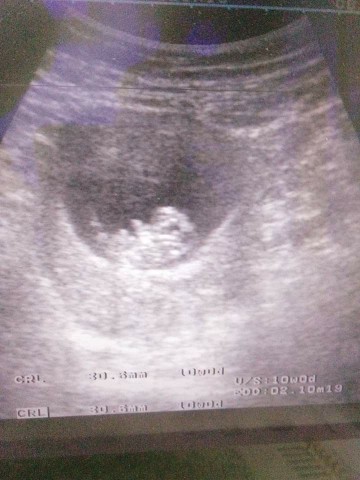

ตอน12วีคคะ ตอนนี้20วีคแล้ว